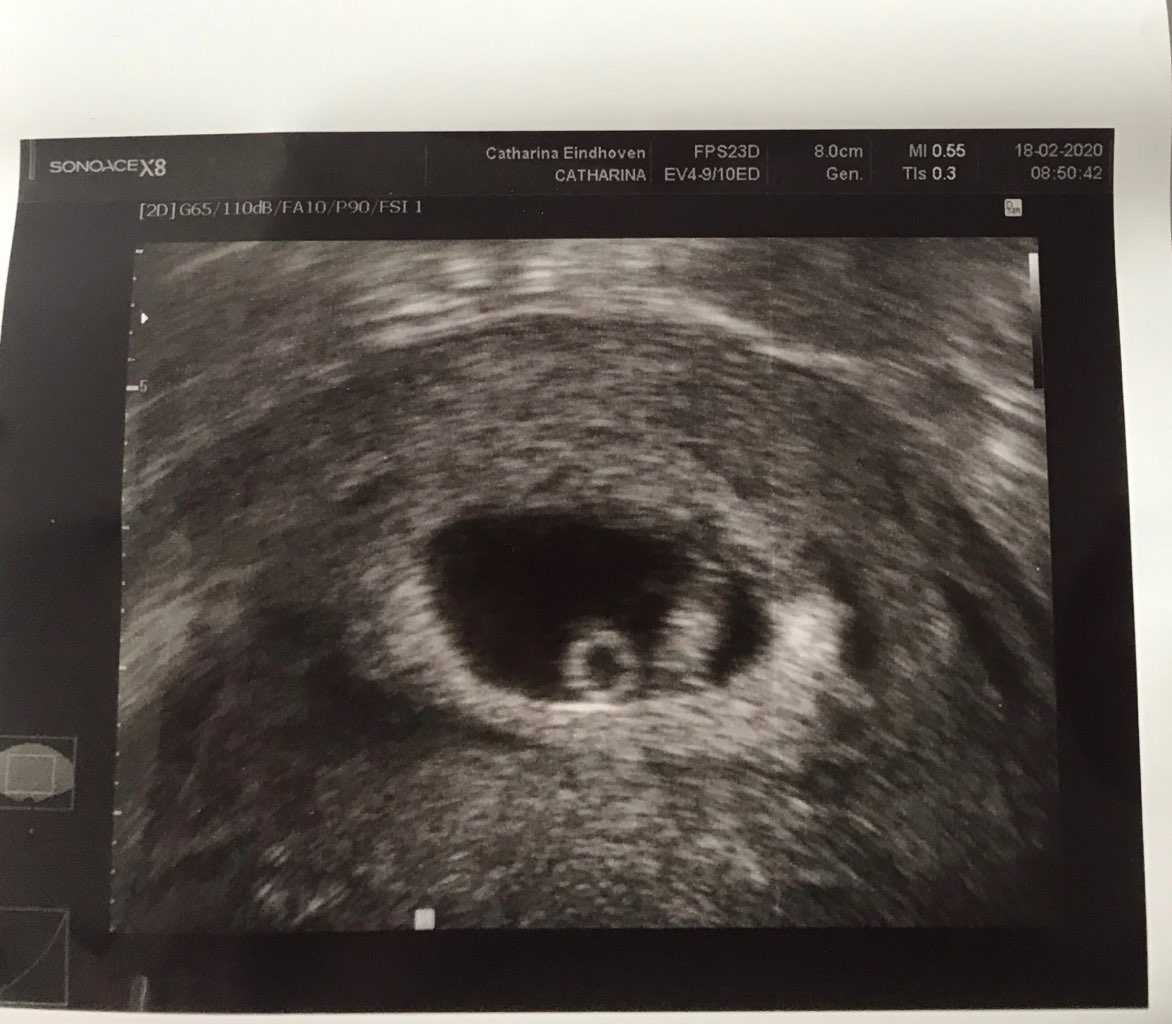

u mnie w 26dpt dopiero co majaczył zarodek, nawet nie szło go zmierzyć. W 33dpt piękny zarodek z sercem pomiędzy zdjęciami jest tydzień różnicy pierwsze 26dpt i drugie 33dpt jeśli jest pecherzyk zoltkowy jutro już powinien być zarodek

Załączniki

• IMG_1903.jpeg

IMG_1903.jpeg

146,1 KB · Wyświetleń: 101

• IMG_1882.jpeg

IMG_1882.jpeg

120,9 KB · Wyświetleń: 103